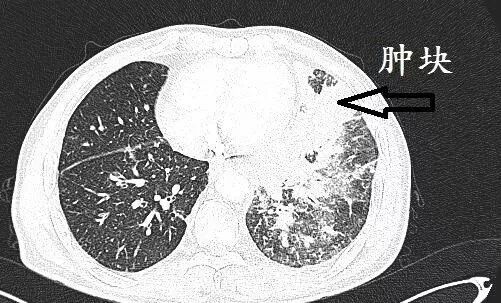

弥漫小叶间隔增厚,肿块,很多是肺癌。哪种肺癌?很多是肺腺癌。这就是肺腺癌引起的癌性淋巴管炎

肿块,结节,在肺部外周,毛刺,分叶,胸膜牵拉,几乎是肺癌,并且,大部分是腺癌,准确性接近90%

细支气管进入肿块,几乎是腺癌